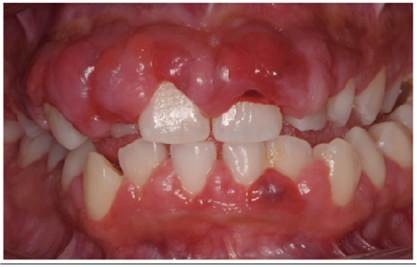

Gingival hyperplasia is an enlargement or overgrowth of the gum tissue, also known as the gingiva, around the necks of the teeth. It is an increase in the size of the gingival tissues and thus the term overgrowth is many times used in place of the term hyperplasia.

Gingival overgrowth can be caused by several mechanisms but will have very similar appearances. A study in the journal Histopathology describes the condition as "a small papillary or velvety bright red gingival overgrowth that bleeds easily." However, the overgrowth can be extensive and round in appearance. It is usually found on the front of the teeth and can be on the tongue side in some cases.

One of the causes is inflammation. The inflammation can be induced by poor oral hygiene or from a dental appliance like orthodontic braces. Other factors include systemic conditions (like hormonal imbalances or leukemia), medications or heredity conditions, according to the American Academy of Oral Medicine (AAOM). Also, localized overgrowth can be a benign or malignant lesion.